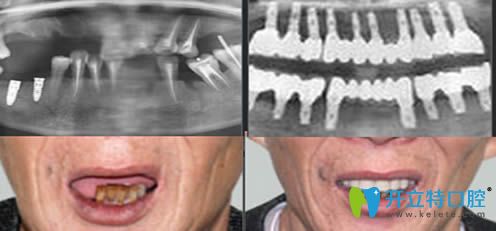

重慶皇仕口腔半口牙種植案例效果前后對比:

顧客:王先生

牙齒狀況:上牙及部分下牙缺失

治療方案:激光無痛即刻種植技術(shù)

完成時(shí)間:3小時(shí)

種植感言:3個(gè)小時(shí)就解決了多年的缺牙問題,顯年輕不說,關(guān)鍵是能和年輕時(shí)候一樣吃東西了,對效果非常滿意。